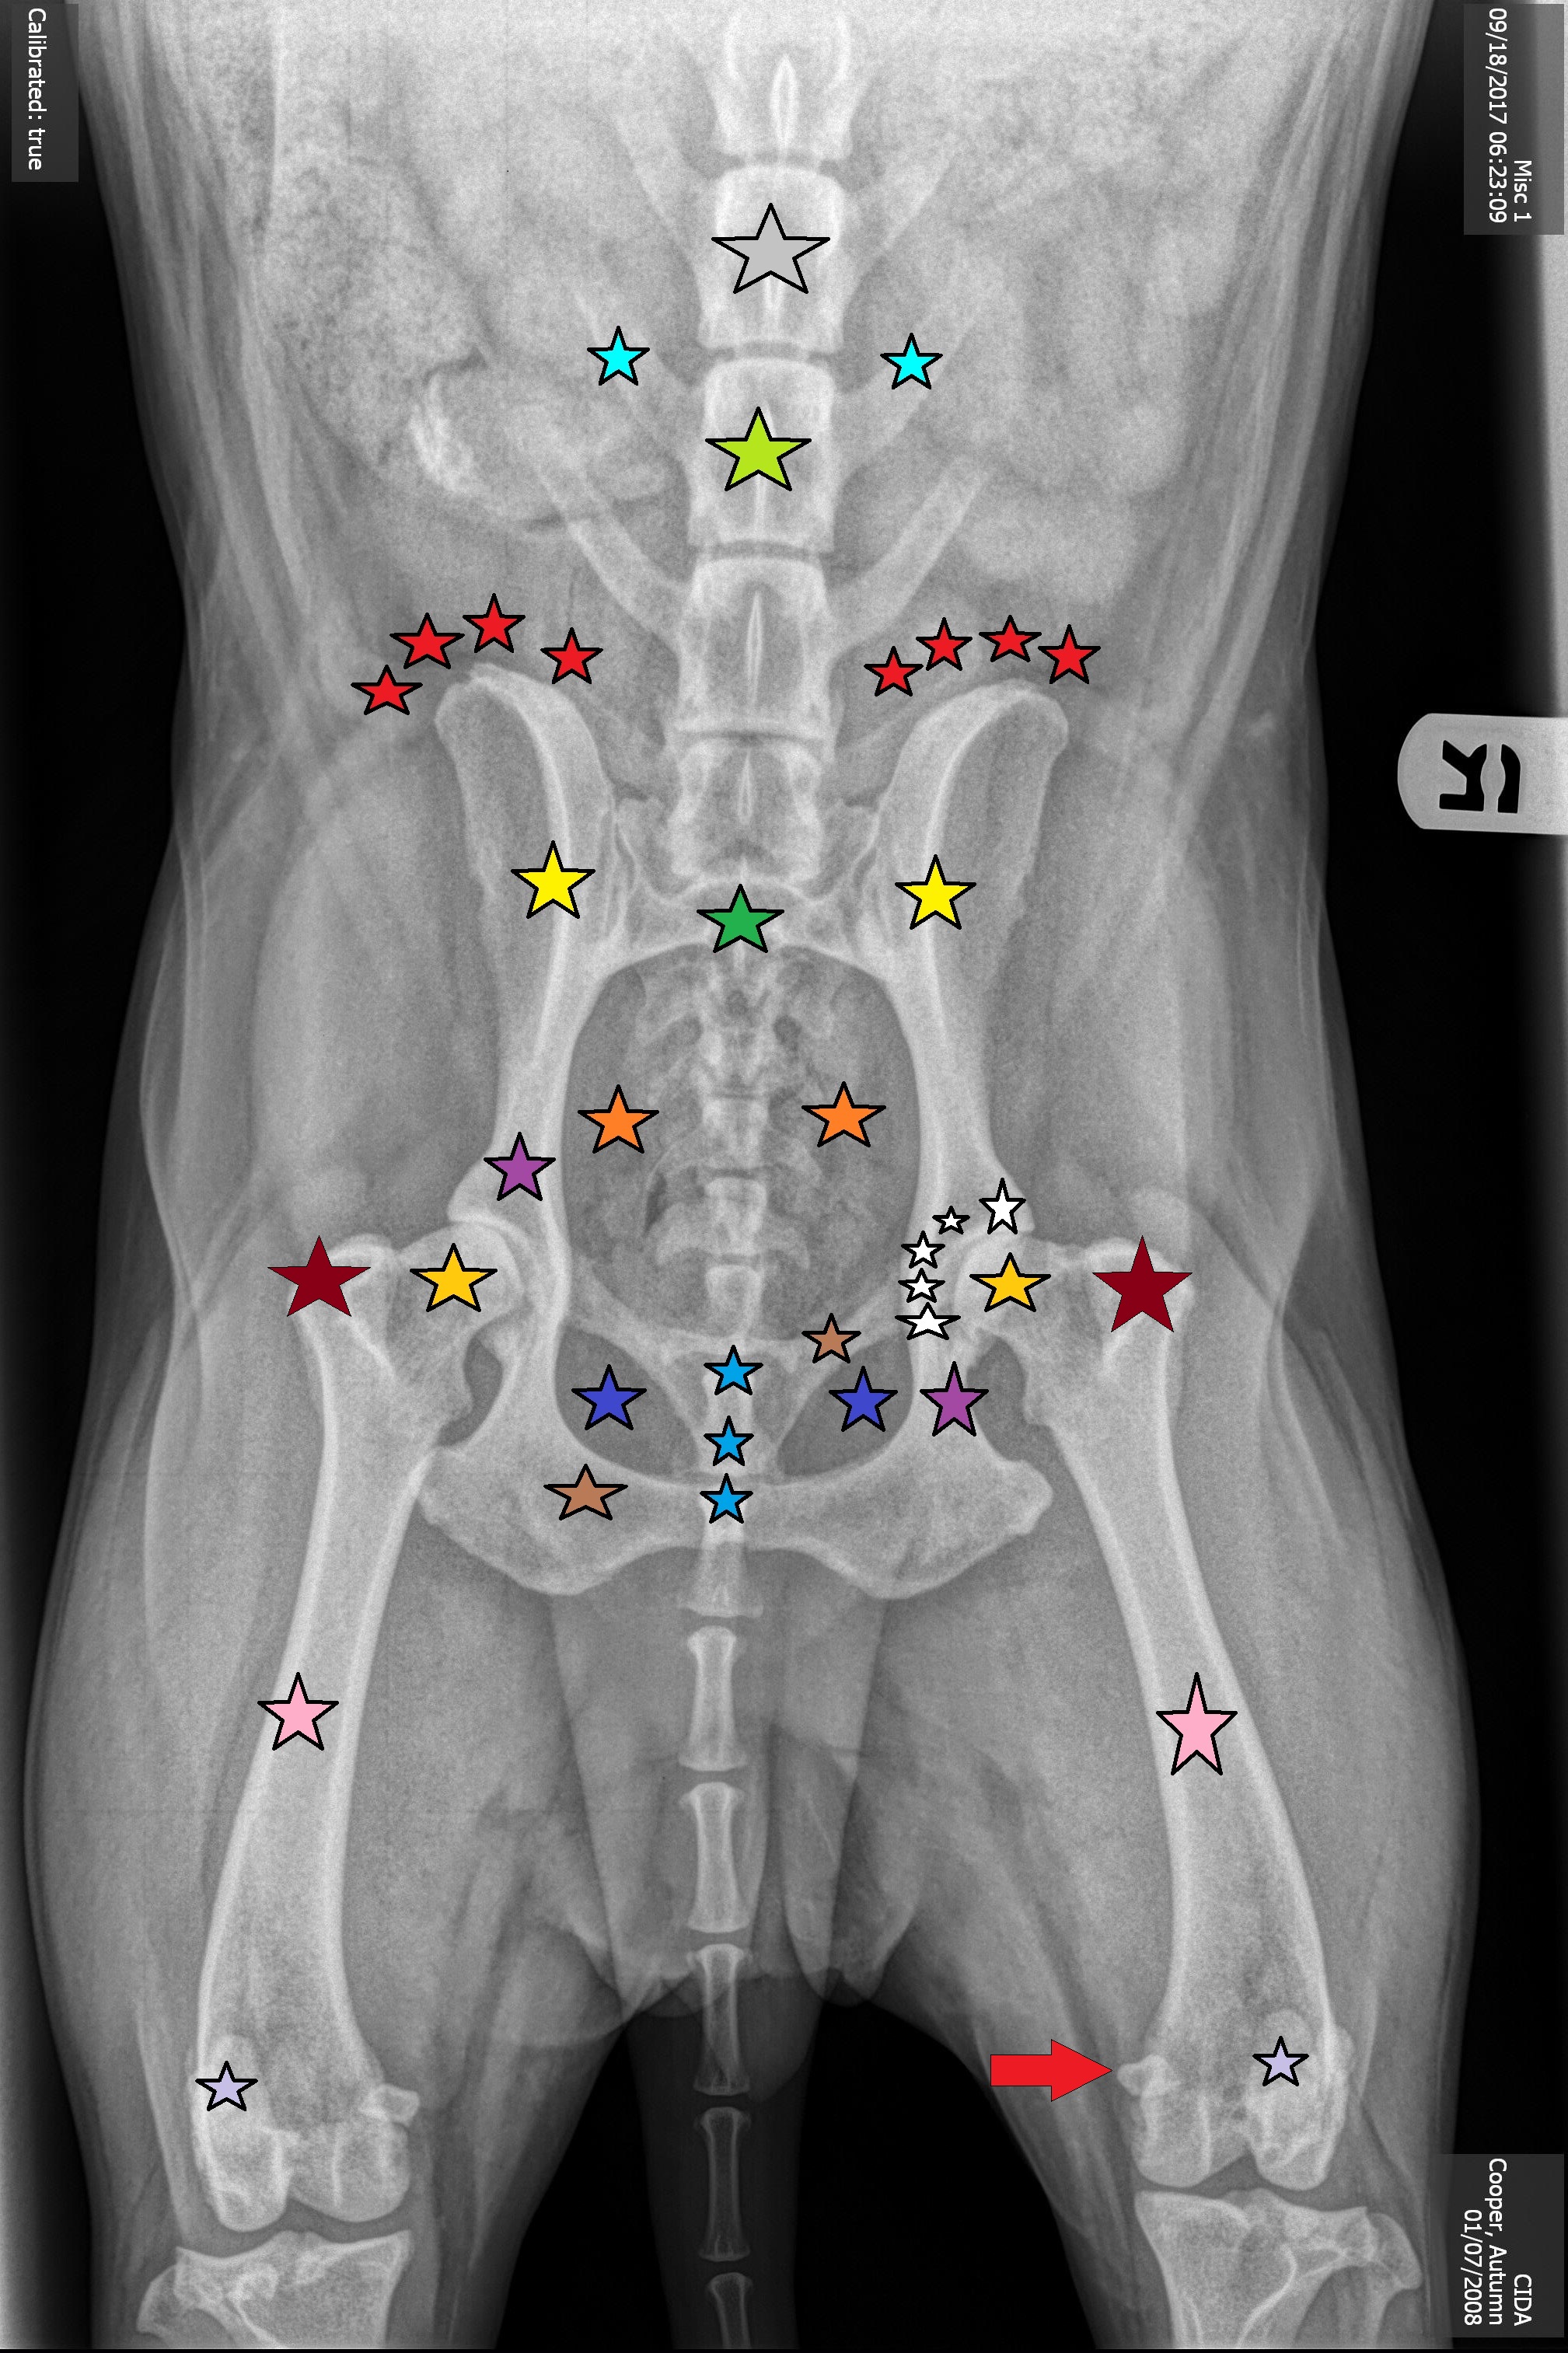

Gray Star

Lumbar Vertebrae #4, L4

Bright Blue Stars

Transverse Processes of L5

Neon Green Star

Lumbar Vertebrae #5, L5

Red Stars

Wings of Ilium

Yellow stars

ilium

Green Star

Sacrum

Orange Stars

Pelvic Outlet

Dark Purple Stars

Ischium

Dark Blue Stars

Obturator Foramen

Blue Stars

Pubic Symphysis

Brown Stars

Pubis Bone

Gold Stars

Head of the Femur

Maroon Stars

Greater Trochanter

White Stars

Acetabulum

Pink Stars

Femur Bone

Light Purple Stars

Patella Bone

Red Arrow

Medial Sesamoid Bone